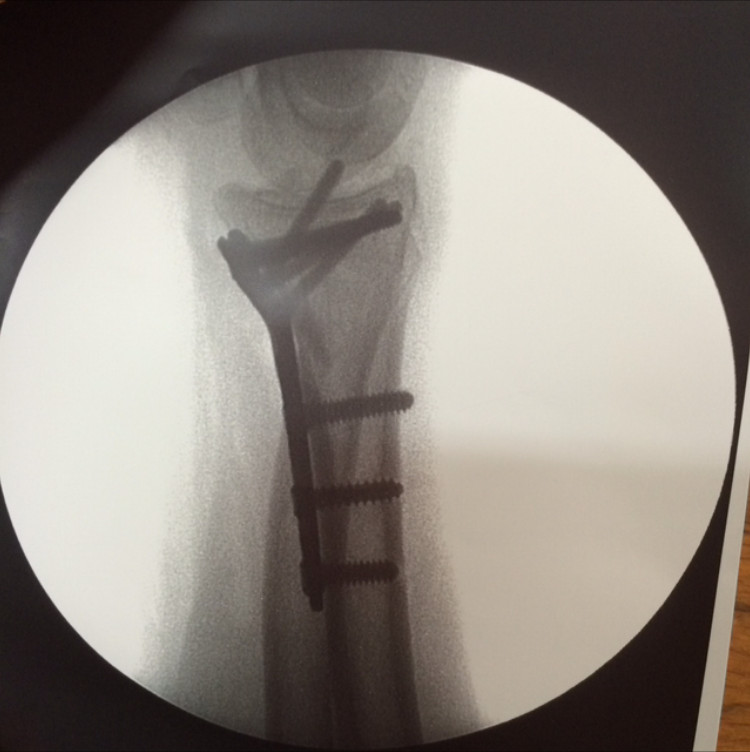

- Osteosynthèse par plaque: c'est la technique plus utilisée. A travers une voie d'abord

chirurgicale : la peau et les tissus sous-jacents sont ouverts sur plusieurs centimètres afin

d'exposer le foyer de fracture. La fracture est alors réduite : le chirurgien mobilise les

fragments osseux avec différents instruments pour les remettre en " bonne position ". La

plaque est alors fixée à l'os par des vis.

- Cas 1 (fractura de radio distal intraticular tratada con placa)

- Cas 2 (fractura conminuta de radio tratada con placa larga)